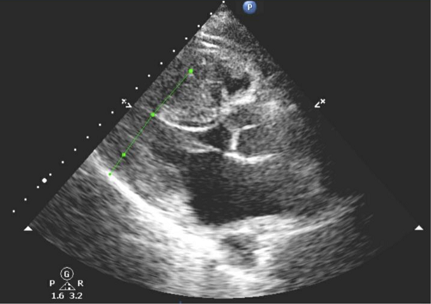

【112-2 醫學(三) 第8題】27歲男性病人與好友熬夜玩電玩,翌日清晨突然倒地急救,經119 EMT施行心肺復甦術,30分內送抵急診,中間多次VT/VF並施行DC shock,到院後CPCR共50分及電擊5次,除了急救藥物使用之外,並在50分鐘內找心臟外科醫師放置葉克膜。病況穩定後進行身體檢查,體溫35.4°C、HR:80/min、RR:20/min、BP:125/68 mmHg,聽診呈現心尖及lower left sternal border(LLSB)有grade 3/6 systolic murmur。緊急冠狀動脈血管攝影顯示無冠狀動脈狹窄或血栓阻塞。心電圖跟心臟超音波如附圖所示。下列何者敘述錯誤?

這位年輕病人突發惡性心律不整(VT/VF),心電圖顯示左心室肥大,心臟超音波可見心室壁增厚,且冠狀動脈攝影正常,這些線索強烈指向肥厚型心肌症(Hypertrophic Cardiomyopathy, HCM)。題目要求找出關於此疾病治療的「錯誤」敘述。